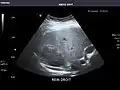

Abdominal Ultrasound (Full Exam)

STRUCTURED REPORT

(Technique: Transabdominal ultrasonography; Device: Toshiba Aplio XG)

Liver: Diffusely homogeneous and normal in echogenicity. No focal mass or contour nodularity. No intrahepatic biliary ductal dilatation.

Portal Vein: Patent main portal vein.

Gallbladder: No stones, wall thickening, or pericholecystic fluid.

Common Bile Duct: Nondilated measuring 1.3 mm at the level of the porta hepatis.

Pancreas: Visualized portions unremarkable.

Spleen: Normal in size.

Kidneys: Right and left kidneys measure 11.5 cm and 12 cm in length respectively. No hydronephrosis. Small left lower pole kidney cyst.

Ascites: None.

Aorta: Visualized portions normal in caliber, 16 x 15 mm.

IVC: Normal.

IMPRESSION:

Normal abdominal ultrasound.